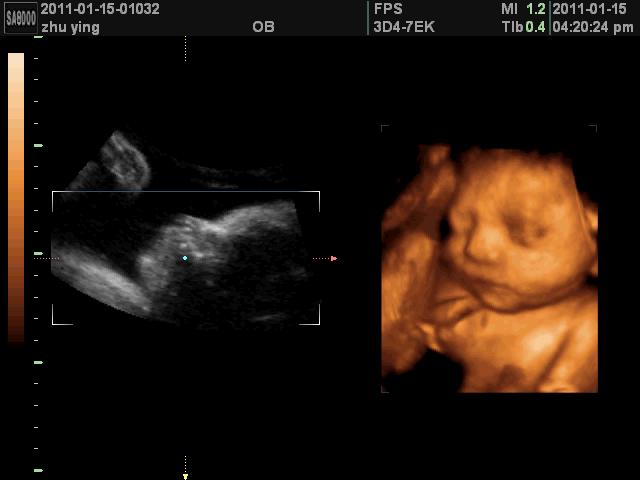

最后来个可爱的四维照!

有没有觉得宝宝可爱到爆!